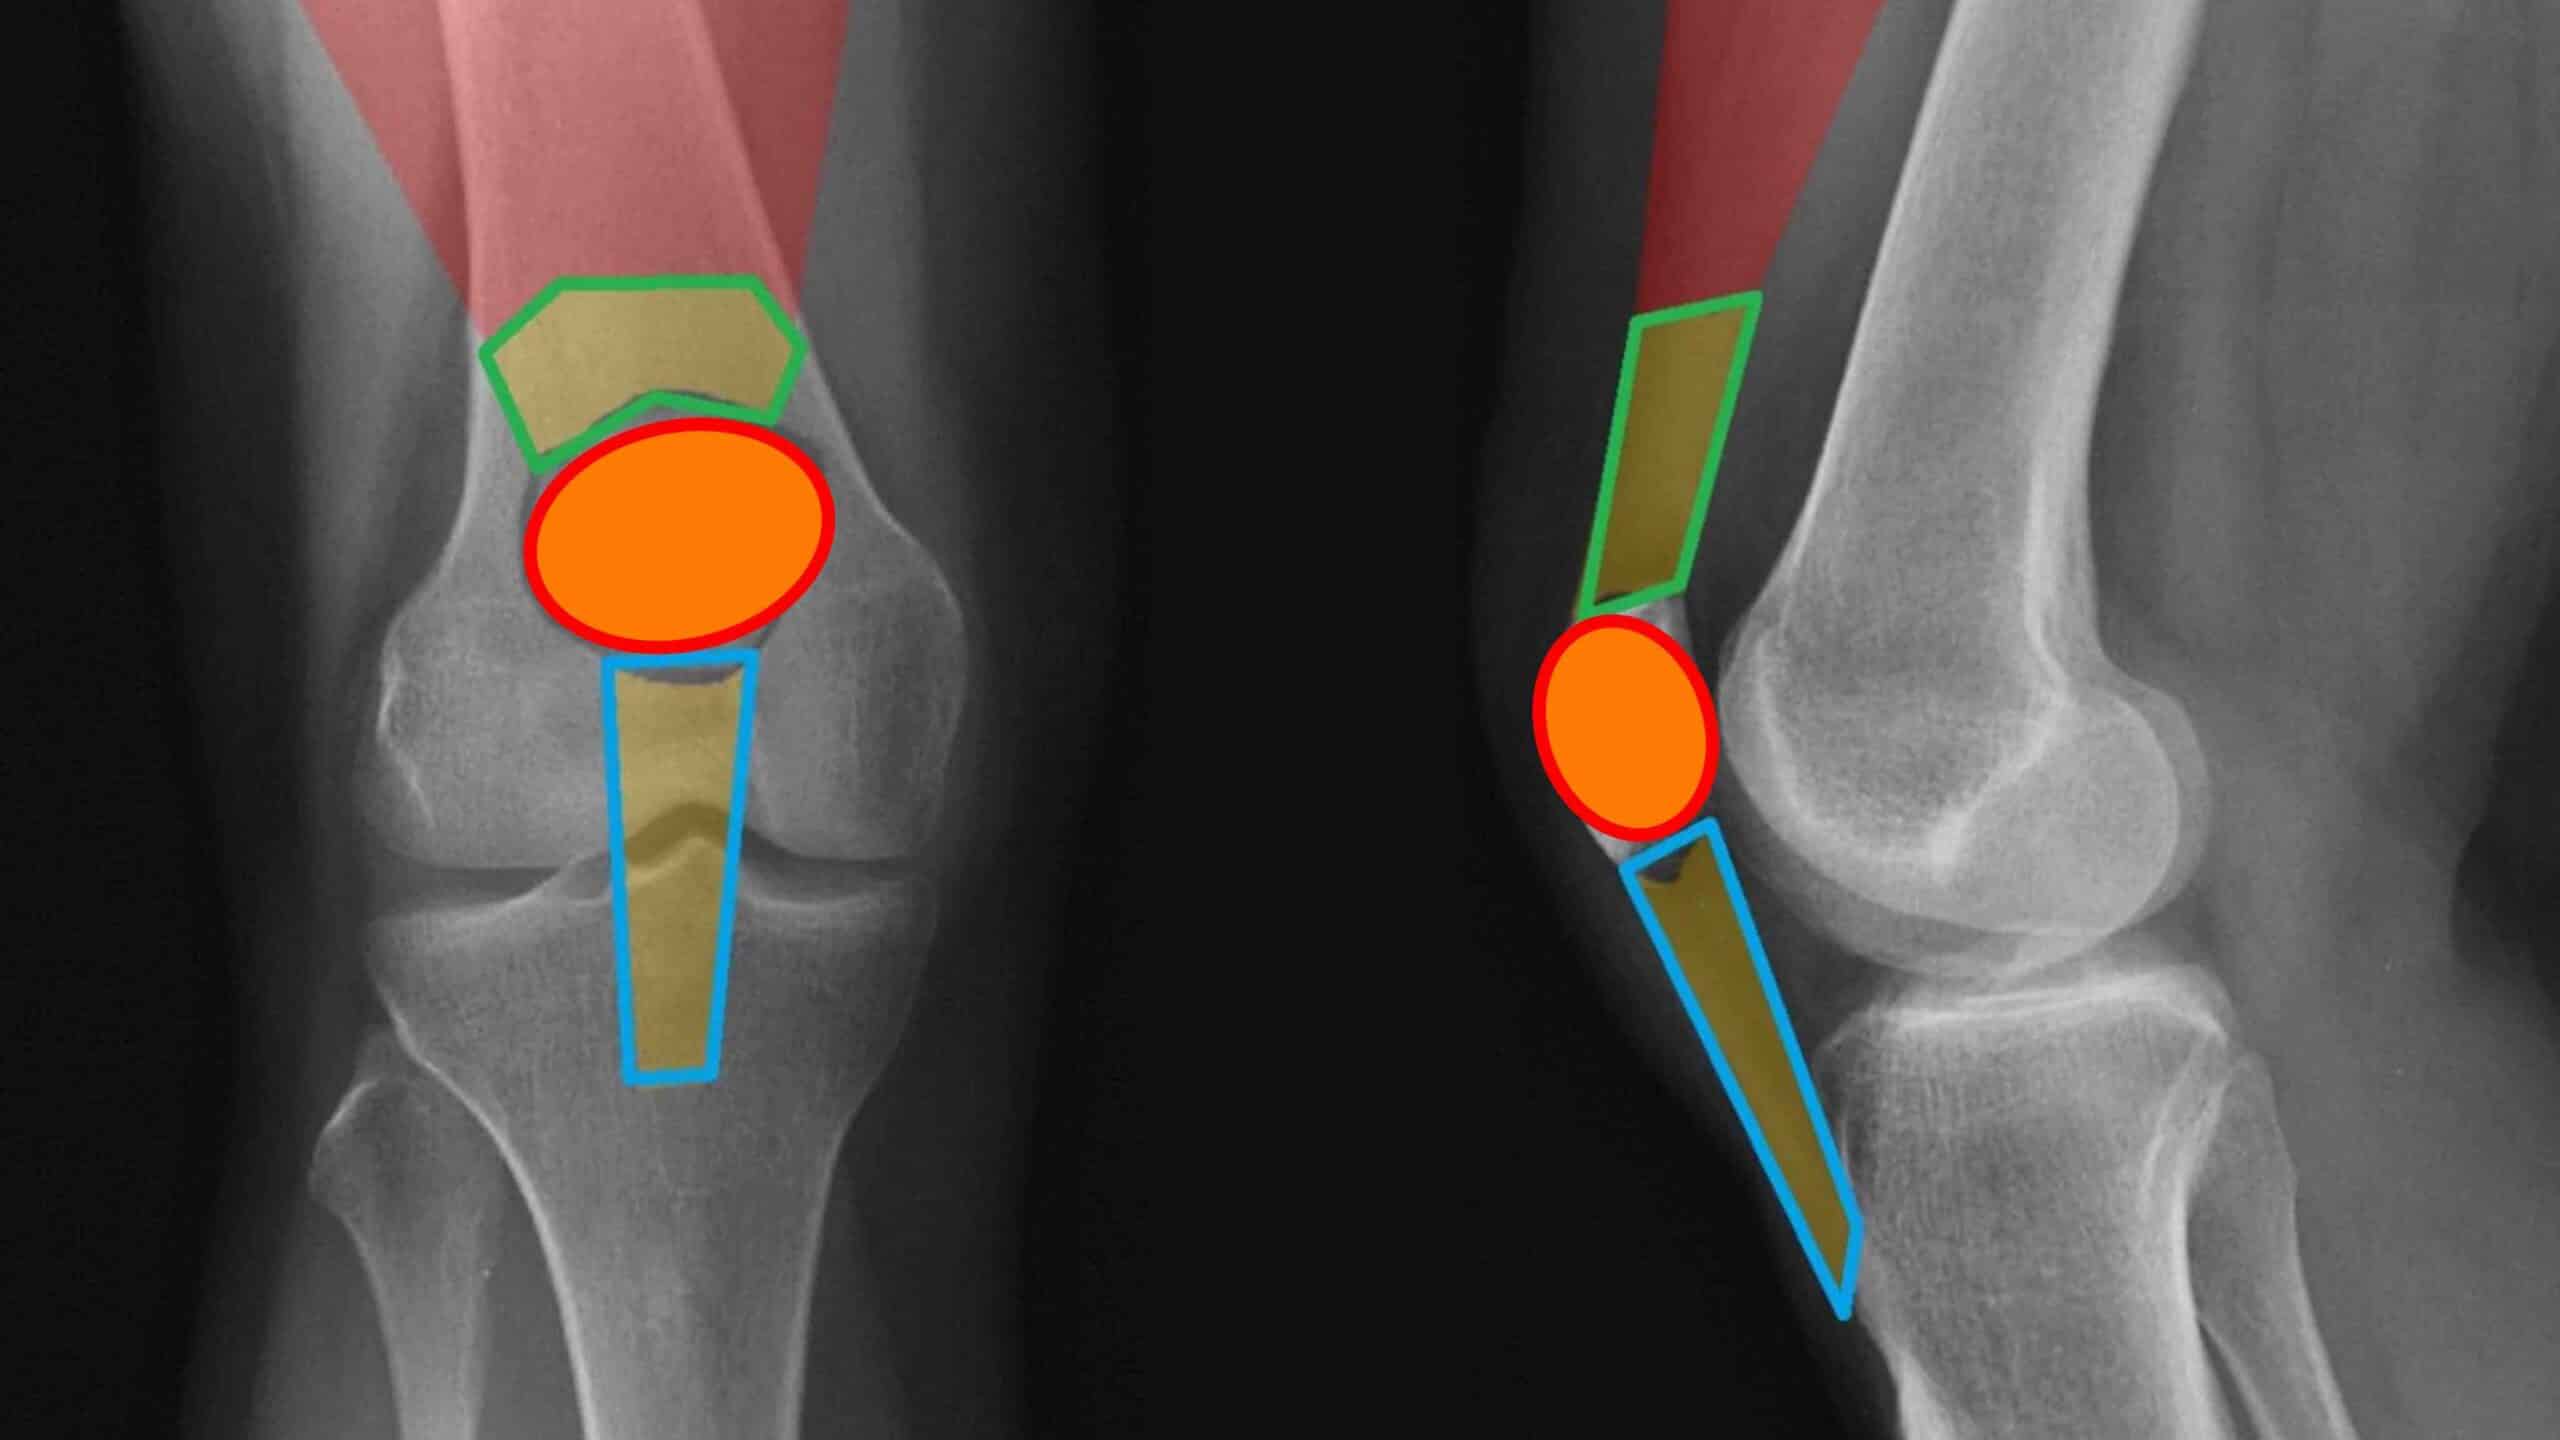

Patelectomia é o procedimento cirúrgico que consiste na ressecção parcial ou total da patela, o osso móvel localizado na frente do joelho. A patelectomia é um procedimento cirúrgico de exceção. É o último recurso, indicado em casos de lesões graves, tumores ou doenças degenerativas da patela. A patela desempenha um papel fundamental na biomecânica do joelho e na força da perna e a sua preservação, sempre que possível, deve ser tentada.

Patelectomia é uma intervenção cirúrgica que consiste na retirada parcial ou total da patela, o osso sesamóide localizado na frente da articulação do joelho. A função principal da patela é servir como uma polia, aumentando a eficiência do músculo quadríceps femoral para estender a perna. Atualmente, graças aos avanços da medicina regenerativa e das próteses de joelho, a patelectomia total é considerada uma técnica cirúrgica de exceção. Os médicos ortopedistas especialistas em joelho fazem o possível para preservar o osso, optando pela remoção apenas quando a reconstrução é tecnicamente impossível.

Existem duas abordagens principais para a patelectomia. Elas dependem da extensão do dano no osso. A patelectomia pode ser parcial ou total. Na patelectomia parcial o cirurgião remove apenas os fragmentos danificados, preservando a maior parte possível do osso sadio. Isso ajuda a manter parte da biomecânica original do joelho. Na patelectomia total o osso é removido por completo. Nesse caso, o cirurgião precisa realizar uma reconstrução do mecanismo extensor, unindo o tendão do quadríceps diretamente ao tendão patelar para que o paciente ainda consiga esticar a perna.